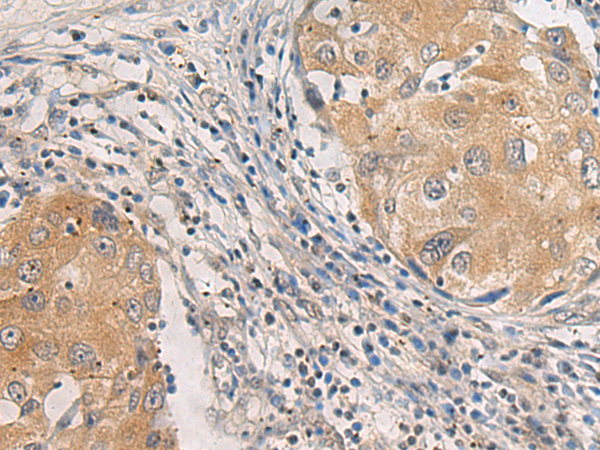

IHC positive control: |

Human thyroid cancer and Human breast cancer |